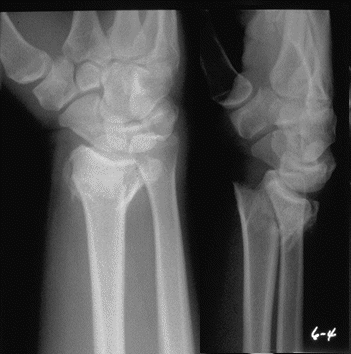

Case 4 Preop